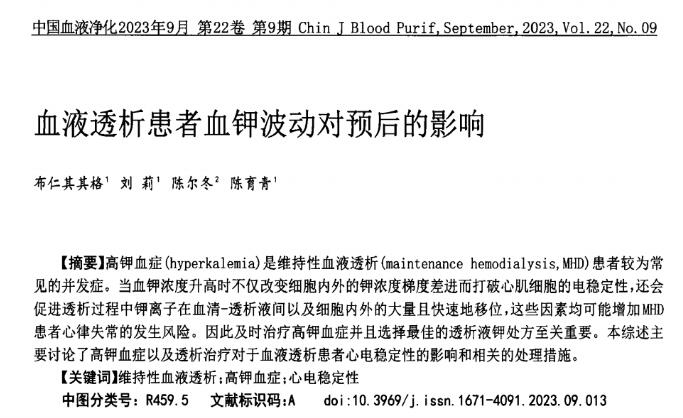

文献速递 | 血液透析患者血钾波动对预后的影响

2023-10-26

了解更多